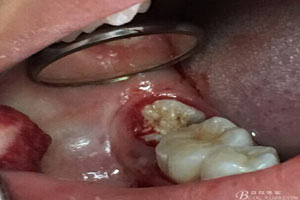

圖3.取出棉球口內(nèi)發(fā)現(xiàn)37合面有開(kāi)髓孔,探針出血,頰側(cè)牙齦紅腫

圖1.患者自述右側(cè)下后牙牙齦紅腫,咀嚼不適。術(shù)前口內(nèi)像:37頰側(cè)牙齦紅腫